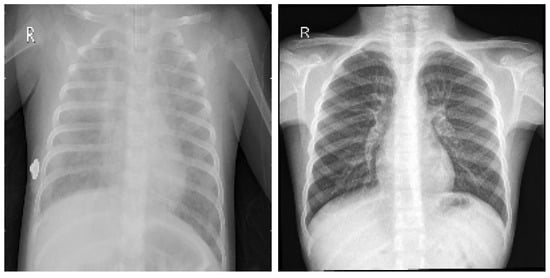

Since lung infections can have multiple causes (not only COVID-19), it is necessary to endow the model with the ability to distinguish COVID-19 infections from other illnesses. Hence, it was necessary to include cases of other possible conditions within the training and testing sets. Great effort was made to obtain as many good-quality images as possible of various types of pathologies. Figure 1 and Figure 2 illustrate samples of pulmonary radiographies of uninfected and COVID-19-infected patients, respectively.

Figure 2. Pulmonary radiography of a person infected with COVID-19.